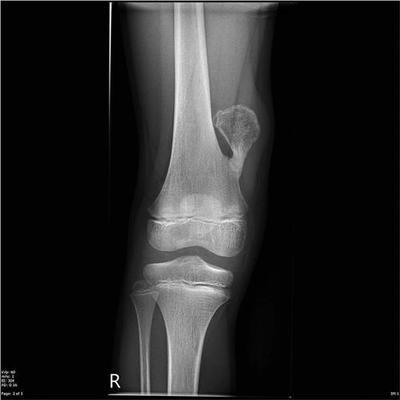

X线片可见近干骺端部位的骨性突起,基底部有时较宽,有时较窄,蒂部与骨干相连,髓腔彼此相通。突起的表面为软骨帽,不显影,所以肿瘤的实际大小可能要比x线平片上要大。和x线相比,CT和核磁共振对位于骨盆、肩胛骨和脊柱上的骨软骨瘤能够更清楚的显示软骨帽的范围及与周围软组织的关系,具有更好的显示效果。

男性多发,肿瘤分布广泛且相对对称。在全身任何存在软骨的骨骼中几乎都有可能发生。由于肿瘤多发,所以很难依据外科手段全部切除。多表现为全身多发的骨性包块,常伴有骨骼短缩和畸形,如膝、踝、肘、腕关节的内外翻畸形。影像学上和单发的骨软骨瘤基本相同,只是肿瘤数量上的不同及存在骨骼畸形而已。